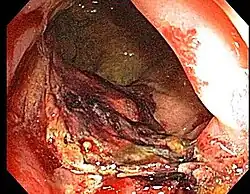

Chronic radiation proctitis

- Chronic Radiation Proctitis

- Etiology: obliterative endarteritis and chronic mucosal ischemia, leading to progressive epithelial atrophy and fibrosis. Ultimately, development of a chronically ischemic intestine prone to fibrosis and bleeding

- Symptoms: diarrhea, obstructed defecation (if strictures), bleeding, rectal pain, rectal urgency, and fecal incontinence. Rarely fistulas, SBO

- Diagnosis: colonoscopy, barium studies if suspecting strictures and fistulas